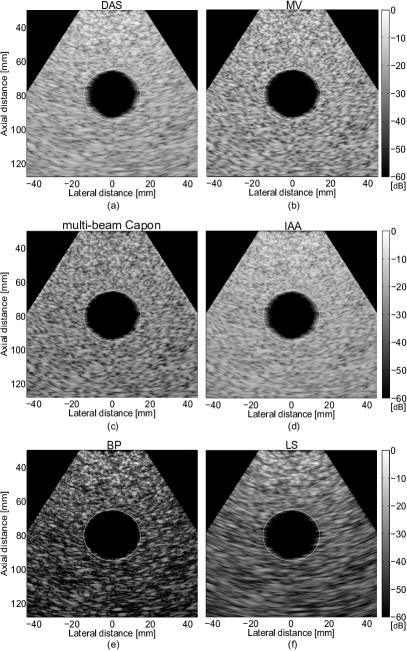

Refer to caption

Figure 8: (a) DAS, (b) MV, (c) multi-beam Capon, (d) IAA, (e) BP, and (f) LS BF results of the ultrarealistic simulation of a cardiac image.

TABLE III: CNR, SNR, and RG values for the simulated US cardiac beamformed images in Fig. 8

BF Method CNR SNR RG

DAS 1.12 0.47 1

MV 0.90 0.56 3.56

multi-beam Capon 0.61 0.54 4.23

IAA 1.30 0.62 5.3

BP 1.45 1.75 9.89

LS 1.55 1.88 2.06

The results of beamforming the cardiac medium are shown in the Fig. 8. With this example, we are interested in visualizing the LV region (hypoechoic), which is surrounded by the hyperechoic regions containing the anterior and posterior walls of the heart as well as the septum. The small echoic regions inside the LV region are the papillary muscles, that due to the low contrast and resolution of the DAS beamformed image are hard to be distinguished, Fig. 8(a). A better visualization of the walls is obtained with MV (Fig. 8(b)) and multi-beam Capon (Fig. 8(c)), resulting also in an improved resolution, confirmed with a higher RG value (see Table III). For the calculation of the CNR, we considered R1subscript𝑅1R_{1} the region inside the white square, situated at approximately 18 mm (laterally) and around 55 mm (axially), while R2subscript𝑅2R_{2} is delimited by the black square, around -20 mm (laterally) and 55 mm (axially). To compute SNR, the R1subscript𝑅1R_{1} region was considered.

An interesting observation is that the value of the CNR in the case of MV and multi-beam Capon is not improved compared with DAS. This is explained by the results in [5], where it has been shown that the improvement of the contrast directly depends on the high definition of the regions (the LV, the septum, and the walls in our example). Since the amplitude of the reflectors from the walls and septum are not so high compared with the region of LV that contains speckle, the contrast of the final image is affected. However, IAA improve both the contrast and the resolution of the image, presenting more defined regions, as shown in Fig. 8(d). Yet, the best improvement of the resolution is obtained when we promote Laplacian BF solutions, with BP BF, see Fig. 8(e), resulting in an improvement by a factor of 2 in RG compared with MV and multi-beam Capon, and by a factor of almost 10 compared with DAS. Of course, as expected, LS BF is highly improving the contrast and the SNR of the resulted image, while the RG is lower than when using the other BF approaches, Fig. 8(f).